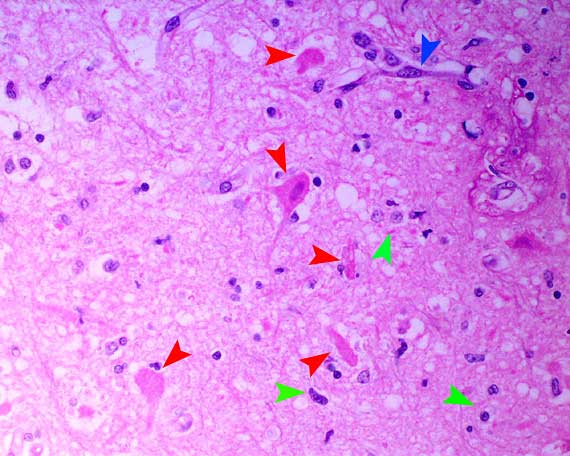

Necrotic neurons - red arrowheads,

gliosis - green arrowheads, reactive endothelium - blue arrowheads.

The appearance of the necrotic neurons is typical of excitotoxic

injury mediated by excessive release of excitatory neurotransmitters

such as glutamate.

Such injury may be seen in cerebral ischaemia, hypoglycaemia,

thiamine deficiency, organic mercurial poisoning, lead poisoning and

in indirect salt poisoning.

In the brain, the neurons that are most vulnerable

to oxygen/energy deprivation lie in certain parts of the cerebral cortex,

cerebellar cortex (especially Purkinje cells), hippocampus, amygdala

and basal and thalamic nuclei and they normally utilise glutamate in

neurotransmission.

A primary cause of seizure activity was not identified

in this dog. A presumptive diagnosis of idiopathic epilepsy with secondary,

seizure-induced, subacute, hippocampal neuronal necrosis was made.